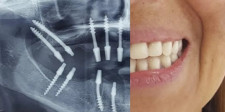

• Implantes dentales:

• Corticobasales (dientes en 72 hora, sin injertos, para pacientes con poco hueso o casi nada de hueso)

• Bifásicos o convencionales (4 meses).